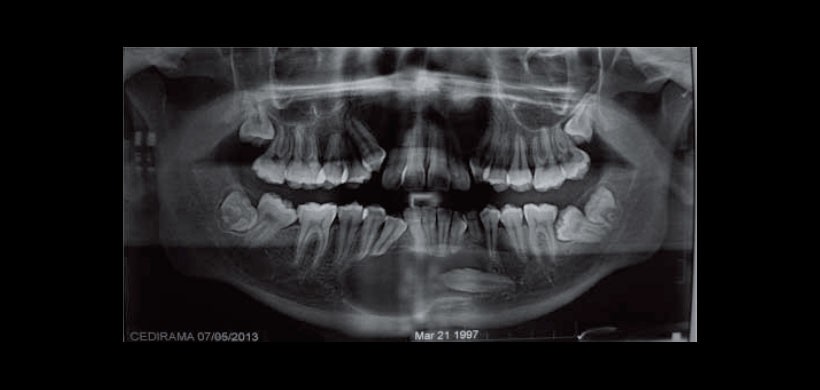

El presente reporte es de un paciente masculino de 15 años de edad, presenta retención de órganos dentales de la primera dentición. Durante el examen clínico intraoral presenta dentición permanente incompleta con malposición dental y presencia de canino inferior derecho deciduo, adecuada coloración e hidratación de las mucosas orales, discreto aumento de volumen en vestíbulo de la región mentoniana con sintomatología dolorosa durante la palpación del mismo, de bordes mal definidos que van desde la zona de canino inferior derecho hasta el contralateral. Motivo por el cual se decide solicitar al paciente ortopantomografía en la cual se observa una imagen radiolúcida de bordes bien delimitados, unilocular, misma que rodea a un órgano dental incluido correspondiente a canino inferior izquierdo permanente, presenta desplazamiento radicular de canino inferior derecho, borde mandibular íntegro (Figura 1). Se decide realizar BAAF de la lesión obteniendo un líquido amarillo, pastoso, espeso, coleccionando aproximadamente 4 cm3, el cual es colocado en laminillas realizando un frotis y para llevarlo a estudio citológico (Figura 2).